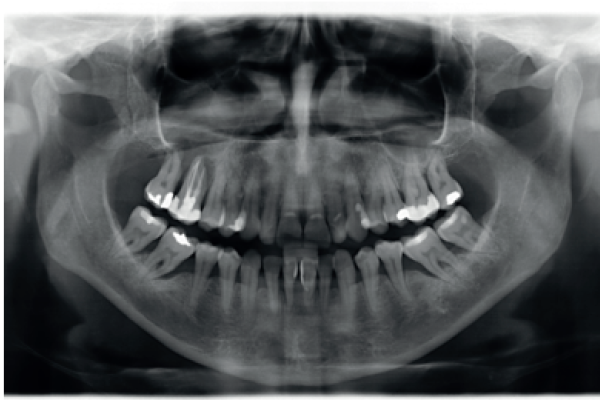

2 | ORIGINAL ARTICLE | RADIOGRAPHIC DIAGNOSIS OF IMPACTED MAXILLARY CANINES: COMPARISON BETWEEN TWO AND THREE DIMENSIONS |